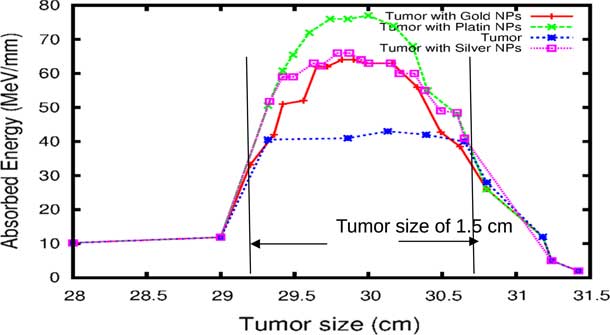

In practice, proton therapy can be used in two ways known as passive scattering and pencil beam. The first technique is based on a single scattering foil (made out of lead) used to broaden the beam. In the second technique, the proton beam is deflected with a magnetic field to generate a narrow monoenergetic pencil beam and scan it magnetically across the tumour. Both of these techniques should be used carefully. Our principal goal is to investigate on how NMs affect on proton therapy. The deposited energy along the head is plotted in the Figure 4. This plot is obtained from a Monte Carlo simulation of 106 protons beam energy of 125 MeV. This figure shows that NMs enhance in a significant way the deposited energy in the tumour. Furthermore, the platinum NPs (PtNPs) present the more efficiency. In order to investigate deeply the enhancing proton therapy by NMs in tumour, we have plotted the deposited energy only along the tumour ranging between 29·2 and 30·8 cm.

Figure 4 The deposited energy of a monoenergetic proton beam along a head. Notes: The Bragg peak energy issued from 106 protons placed at 1 m from the head. The proton beam energy is 125 MeV. Abbreviations: GNPs, gold nanoparticles; PtNPs, platinum nanoparticles; AgNPs, silver nanoparticles.

The comparison of our results concerning the energy deposited into a tumour in the presence of NMs is represented in Figure 9. As the figure shows, the gold and silver enhance the proton therapy and increase the absorbed energy in the tumour up to 55%, on the other hand, platinum increases the absorbed energy up to 80%. Lin et al.Reference Lin, McMahon, Scarpelli, Paganet and Schuemann 25 have compared radiotherapy with protons and radiotherapy with photons and concluded that the proton therapy can enhanced significantly the absorbed dose only if the GNPs are in close proximity to the biological target.

Figure 9 The deposited energy of a polyenergetic proton beam into the tumour with adding nanomaterials (NMs). Notes: The proton beam energy is ranging between 116 and 126 MeV in the tumour without any NMs, and between 116 and 130 MeV in the tumour with gold NPs (GNPs) and silver NPs (AgNPs). In the case of platinum NPs (PtNPs), the proton beam energy is ranging between 116 and 132 MeV.

Although GNPs have been very popular with nanomedicine researchers,Reference Lin, McMahon, Scarpelli, Paganet and Schuemann 25 our findings show that platinum metal is more effective in proton therapy. A French–Japanese research group has demonstrated that PtNPs strongly enhance the biological efficiency of radiations.Reference Porcel, Liehn and Remita 24